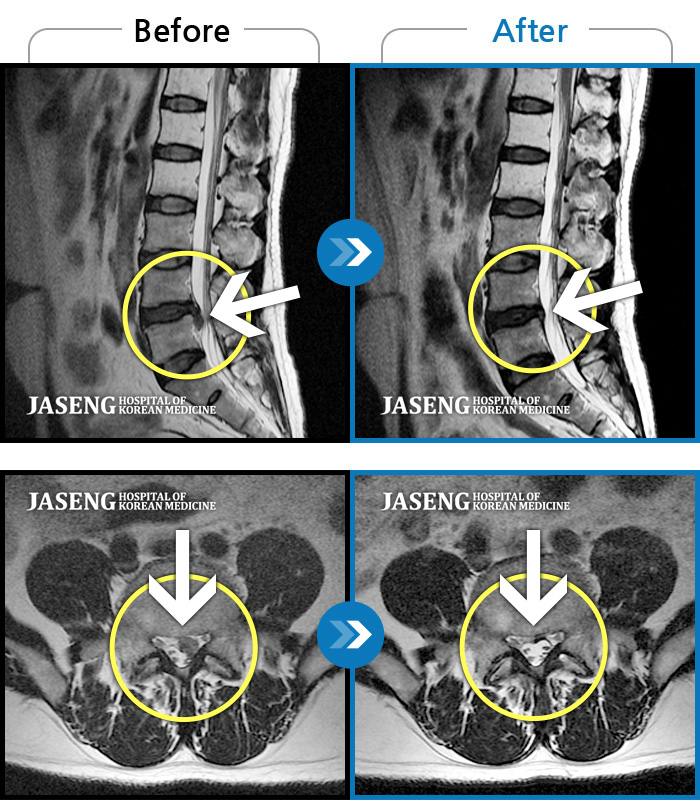

허리디스크

보라매 · 빈상은 원장

허리통증, 좌측 다리 바깥쪽으로 저림이 있어서 양말을 신기도 어려워요.

촬영시기

2022.12.12 ~ 2023.06.10

2023.11.24

조회수 181